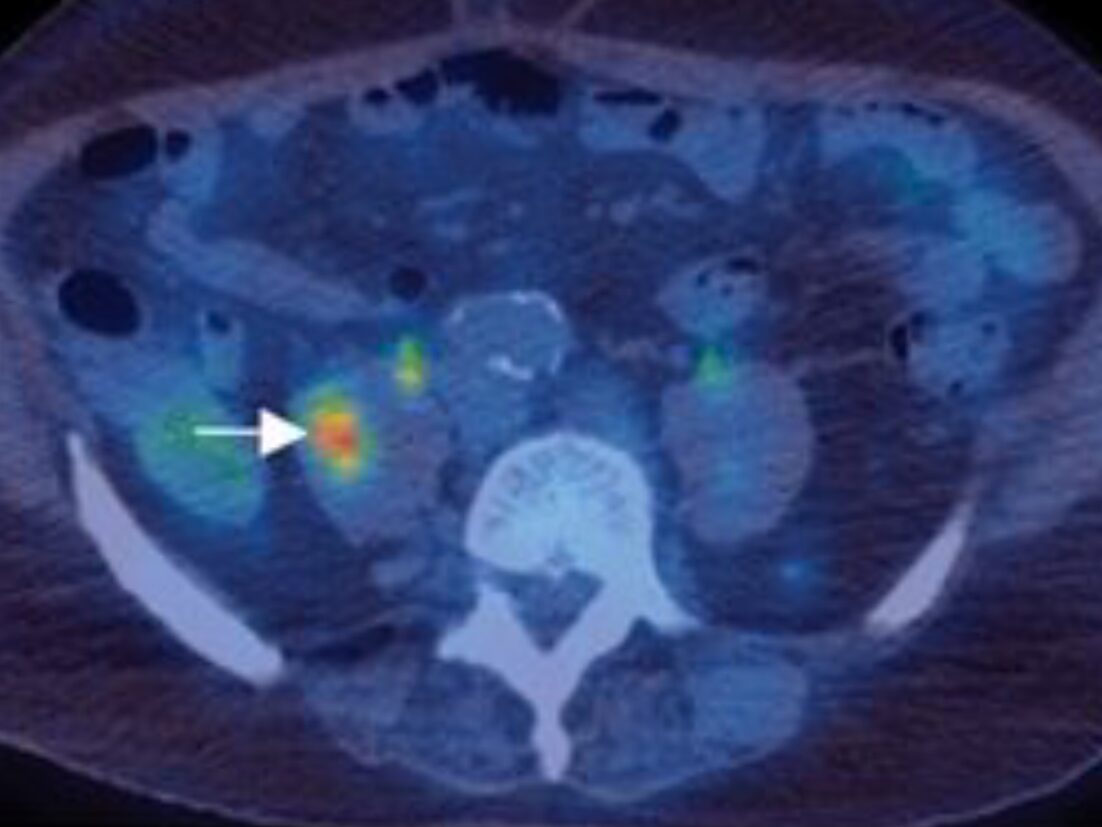

Sometimes these bad cells can even break away from the lump and travel to other parts of the body. This is called metastasis. This is when the cancer becomes very dangerous because it interferes with the function of the organs where it spread to.

The cancer cells invade the underlying connective tissue and penetrate blood and lymphatic vessels. Once in blood and lymph, they can spread throughout the body.